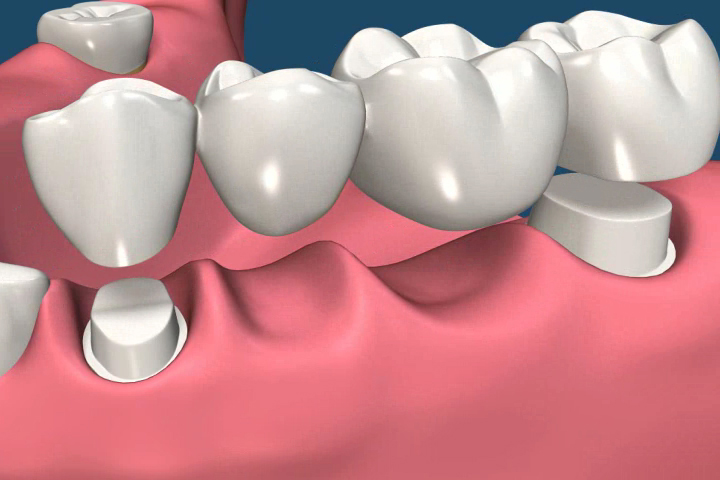

Dental bridge is an affordable, low risk and time tested treatment for lost or missing teeth. It gets this name because it bridges the gap between the teeth. The typical bridge consists of one or more fake teeth known as pontics. These are placed by two abutments or dental crowns. There are different types of dental bridges used in patients to solve the dental issues. They are as follows.

- The dentist crown one of the adjacent teeth in order to place cantilever type of bridge. The single crown can support the tooth restoration which comprises of two pontics.

- Even though most of the bridges are fixed permanently in the mouth of patient some people may also get benefited from removal dental bridges. This is also known as partial denture.